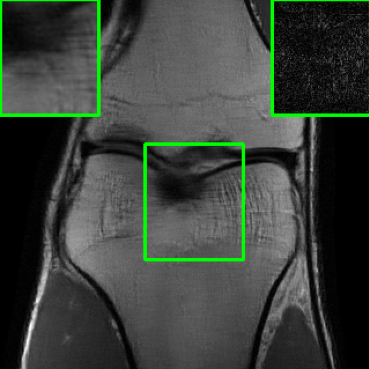

| Ground Truth | MoDL | RS-E2E | AT | Ours |

| PSNR = dB | PSNR = 22.28 dB | PSNR = 25.34 dB | PSNR = 29.47 dB | PSNR = 32.88 dB |

| PSNR = dB | PSNR = 22.23 dB | PSNR = 24.56 dB | PSNR = 29.25 dB | PSNR = 33.18 dB |

5.4 Visualizations

We now present visual samples from both the knee and brain datasets. Specifically, Figure 5 presents visual comparison of image reconstructions and their associated reconstruction errors within a closely examined region. Each image in the figure includes two inset panels in the top-left and top-right corners. The top-left inset panel, enclosed within a green bounding box, serves as a reference for the region of interest in the image. In contrast, the top-right inset panel depicts an error map in relation to the ground truth. Notably, our method stands out in its ability to capture the original image’s features, surpassing the performance of alternative methods (as also evident from the reported PSNR values). This visual comparison underscores the superior quality and accuracy of our approach in the robustification of the MRI image reconstruction task.